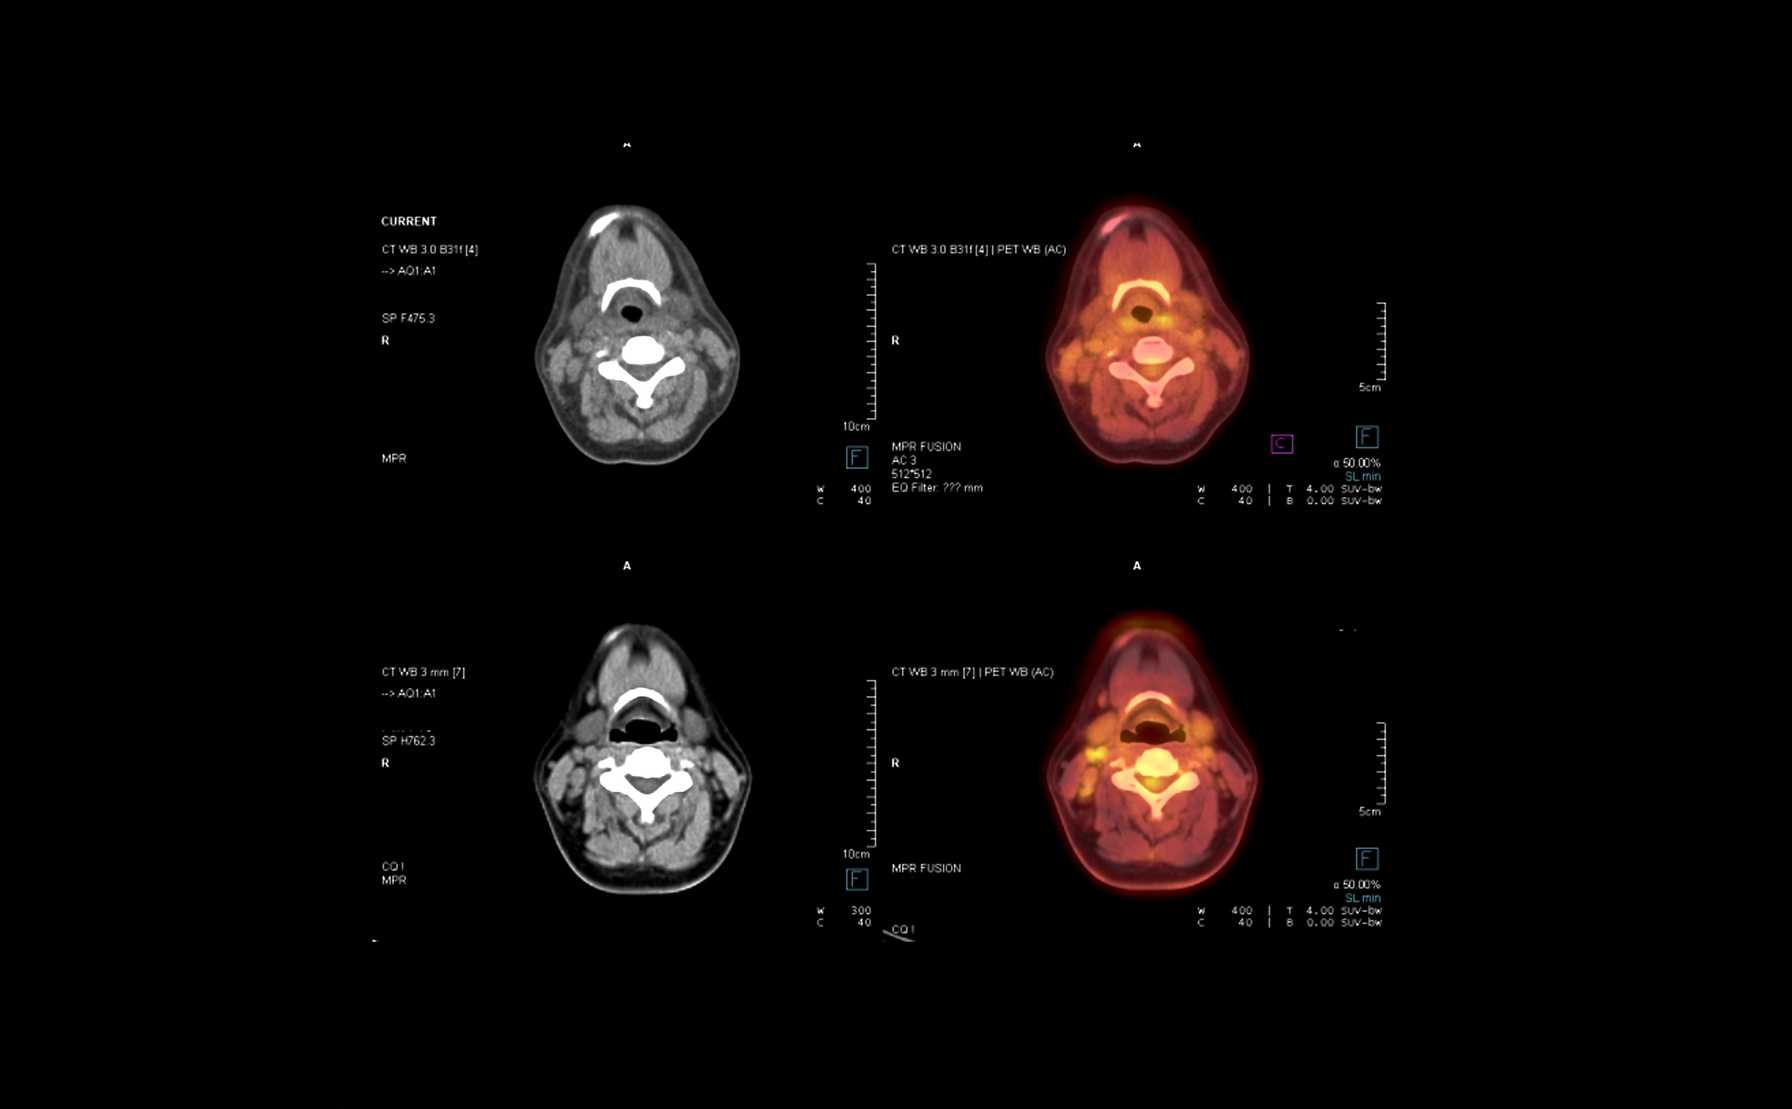

centers in North America utilizing Aura intraoperative PET-CT technology

Molecular and Genomic Profiling of Head and Neck Tumors

- PI: Richard V. Smith, MD

- Sponsor: Montefiore Einstein